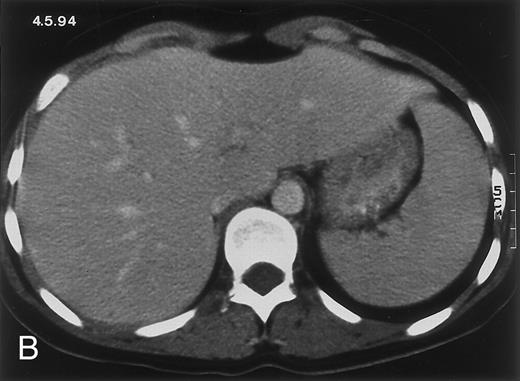

Radiologic evolution in patient B. (A) Postcontrast abdominal CT scan on February 10, 1994 shows multiple small hypodense areas in all segments of the liver suggestive of hepatic candidiasis. Twenty-four days previously, the patient had recovered from severe neutropenia after the second cycle of chemotherapy for ALL. (B) On May 4, 16 days after the neutrophil count had dropped below 500/μL in the third chemotherapy cycle, there is clear improvement of the radiologic findings, with only a few hypodense areas in the liver.

(C) On June 6, 31 days after normalization of neutrophils, CT again shows multiple lesions in the liver (arrowheads) with a different presentation: the small lesions show strong peripheral enhancement. (D) On September 2, 129 days after neutrophil recovery, all hepatic lesions have completely resolved.

Evolution of fungal lesions on CT scans during and after neutropenia is summarized in Table 2. Figure 1 (patient A) and Fig 2 (patient B) serve to illustrate Table 2.

In three patients, multiple round lesions were seen on postcontrast CT scans of the abdomen in the liver and the spleen, while in two cases, lesions could only be seen in the liver (Table 2). Following the diagnosis of disseminated candidiasis, these lesions decreased in size and visibility during subsequent neutropenia in three patients (compare Fig 2A and B) and disappeared completely in two patients (compare Fig 1A and B). The numbers of days of severe neutropenia (neutrophils <500/μL) at the time the CT scan was performed are listed in Table 2. After recovery from neutropenia and despite continued antifungal therapy, the size and visibility of the lesions increased again (Fig 1C). Similarly, the number of days since recovery from severe neutropenia (neutrophils >500/μL) are listed in Table 2. In two of three patients treated with another cycle of myeloablative chemotherapy, this waxing and waning pattern of radiologic lesions could be seen again (Fig 1D and E). In all patients, lesions eventually disappeared (Figs 1F and 2D) after prolonged antifungal therapy.